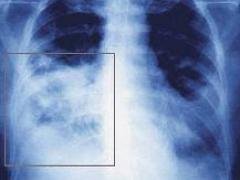

В Кыргызстане с марта 2016 года планируется вакцинация младенцев против пневмонии